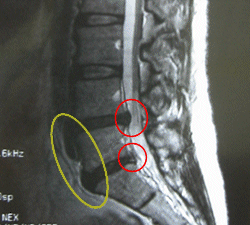

■腰の骨側面

腰の骨4番ー腰の骨5番、腰の骨5ー仙骨の間が、飛び出しているのが見られます。(赤丸)

腰の骨の前面にも飛び出して、変性しているのが見られます。(黄色丸)